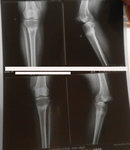

Дата операции 14.04.2016г.

Дата снятия аппаратов 01.08.2016г.

Срок лечения 106 дней.